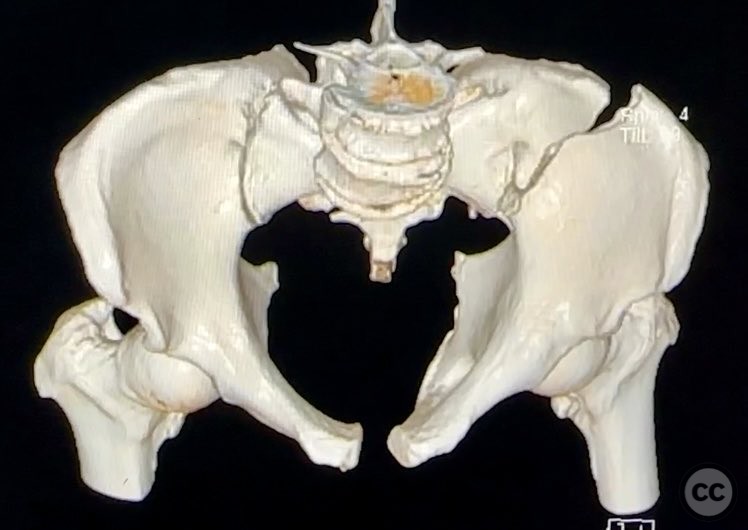

Complete Iliac Fracture with Symphysis Pubis Disruption and Contralateral Incomplete SI/Iliac Fracture

Clinical Details

Clinical and radiological findings:  A patient sustained a high-energy pelvic ring injury characterized by a complete left iliac fracture extending from the iliac crest to the greater sciatic notch, associated with a complete disruption of the symphysis pubis (SP). Additionally, there was a less displaced, incomplete right sacroiliac (SI)/iliac fracture. The injury pattern is consistent with an AO/OTA 61-B2.3 (lateral compression type II) pelvic ring injury. No neurovascular compromise or significant soft tissue injury was reported.

Preoperative Plan

Planning remarks:  The preoperative plan included open reduction and internal fixation of both the iliac fracture and the symphysis pubis disruption. The anatomical approach was planned via direct anterior exposure to the symphysis pubis and an ilioinguinal approach to the iliac wing fracture, with reduction maneuvers at both the iliac crest and pelvic brim.